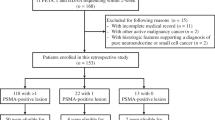

In this study, n = 66 patients with advanced mCRPC, who received [177Lu]Lu-PSMA-617 RLT in a palliative setting, were analyzed. Patients were treated at our institution within a prospective patient registry (REALITY Study, NCT04833517). Inclusion criteria for this study were confirmed mCRPC, at least 2 cycles of [177Lu]Lu-PSMA-617 RLT, [68Ga]Ga-PSMA-11 PET/CT before the first and after the second cycle of [177Lu]Lu-PSMA-617 RLT, absence of [18F]FDG/[68Ga]Ga-PSMA-11 mismatch findings (if additional [18F]FDG-PET/CT was performed), and availability of clinical outcome data. All patients received multiple therapies prior to PSMA-RLT, including ADT, NAAD, chemotherapy, and [223Ra]Ra-dichloride therapy. Detailed information about the patient characteristics is presented in Table 1. Between both PET scans, ADT and NAAD had to be continued unchanged to avoid altering PSMA expression [31]. PSMA-RLT was performed on a compassionate use basis under the German Pharmaceutical Act §13 (2b). Patients gave their consent after being thoroughly informed about the risks and potential adverse effects of PSMA-RLT. In addition, the patients agreed to the publication of the resulting data in accordance with the Declaration of Helsinki. The study was approved by the local Institutional Review Board (ethics committee permission number 140/17).